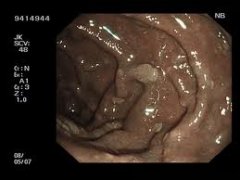

Ved klassisk FAP ses fra 100 til over 5000 adenomer i tyktarmen og endetarmen, og alle patienter har adenomer i endetarmen. Adenomerne opstår hyppigst i 10-20 års alderen og sjældent efter 40 års alderen.

Fundic gland polypose ses hos flertallet som hundredevis af små polypper opadtil i mavesækken. De vil aldrig omdannes til kræft og kontrol er derfor unødvendig.

Duodenale polypper (adenomer) udvikles i tolvfingertarmen hos over 90 %. På baggrund af polypantallet, størrelsen, typen og graden af celleforandringer (bedømt ved mikroskopi af vævsprøver) inddeles duodenal adenomatose efter ”Spigelmans klassifikation” i 4 stadier. I langt de fleste tilfælde ses de mildeste stadier, men regelmæssig kontrol med gastroskopi er nødvendig, da polypperne kan forværres med alderen og især i det sværeste stadium er der risiko for udvikling af kræft.